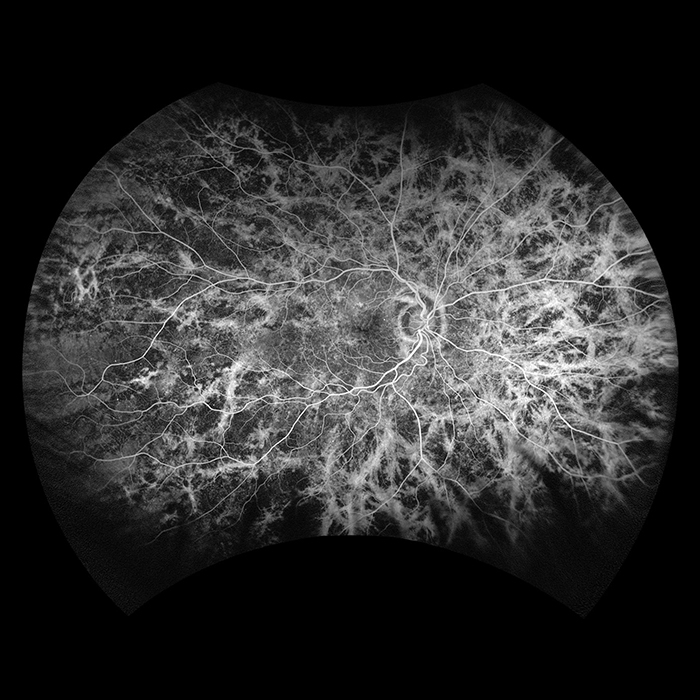

Silverstone, the most powerful tool yet for examining the retina, is the only ultra-widefield imaging device with integrated Swept Source OCT. Silverstone produces a 200° single shot retinal image of unrivaled clarity in less than ½ second and enables optomap guided SS-OCT scanning across the retina and into the far periphery.

optomap has been shown to enhance pathology detection and disease management and to improve clinic flow. Now with integrated Swept Source OCT, Silverstone facilitates examination of the retina from vitreous through the choroidal-scleral interface.

Silverstone imaging modalities and image viewing options:

optomap Image Modalities

- color rg

- Sensory Retina

- Choroidal

- green af

- fa

- icg

- SS-OCT